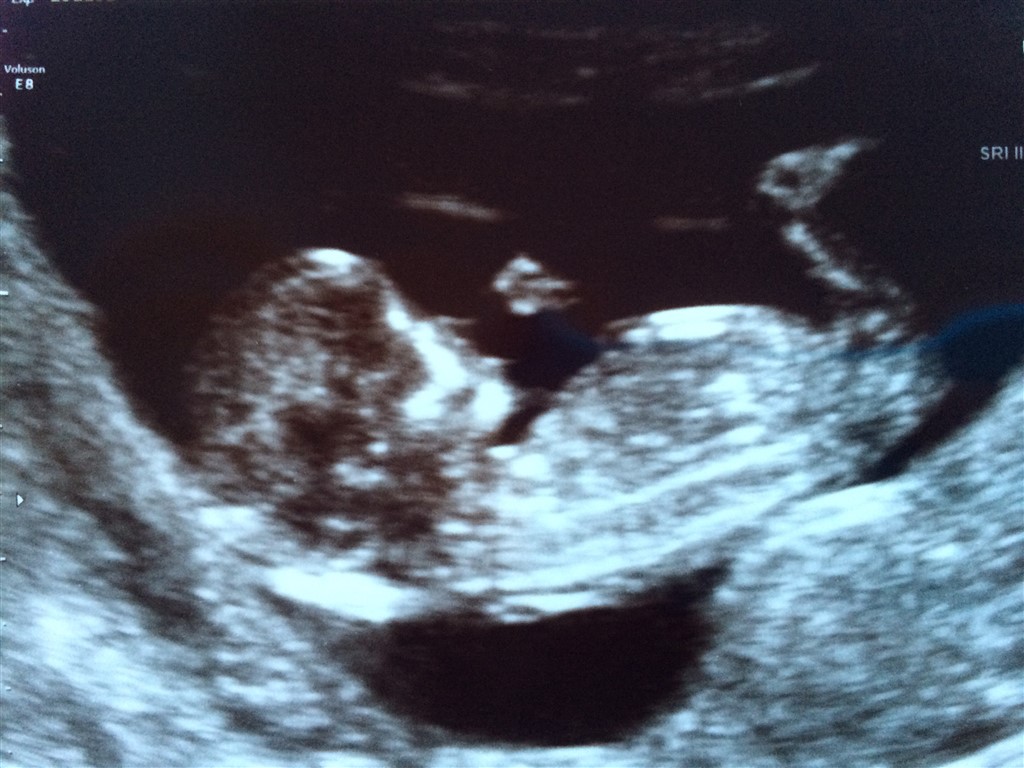

Vi var til NF i torsdags, og vi er jo ved at gå til af spænding over at finde ud af hvilket køn vi venter os! Vi finder først ud af det til MD, men indtil da vil jeg høre om I ikke har et bud?

Vedhæftede fotos (klik for at se i fuld størrelse)